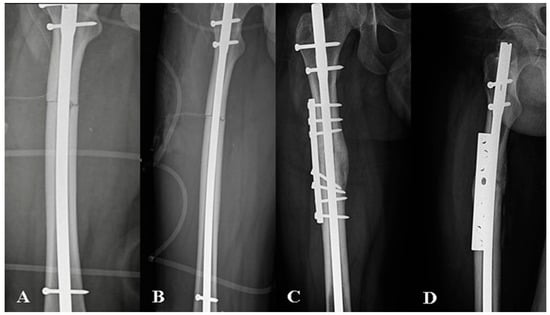

2.4.1. Nail Exchange Technique

2.4.2. Plate Augmentation with Autologous Bone Grafting Technique